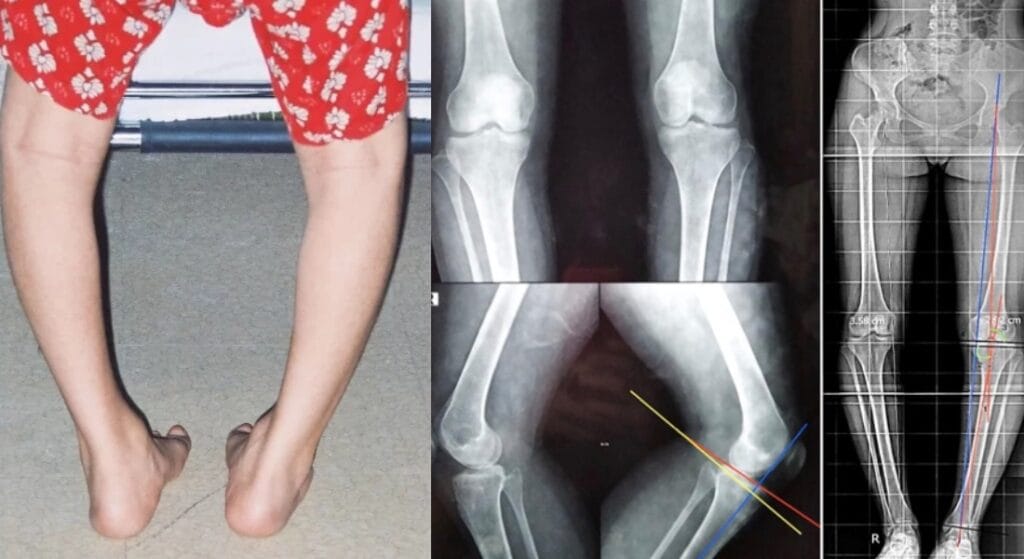

Đối với người trưởng thành, xương đã phát triển hoàn chỉnh nên chân vòng kiềng không thể tự hết. Việc điều trị lúc này chủ yếu nhằm cải thiện hình dáng chân, giảm đau nhức, phòng ngừa các biến chứng (như thoái hóa khớp, lệch trục chân…). Một số trường hợp cong nhiều, đau dai dẳng hoặc biến dạng nặng, bác sĩ có thể đề nghị các biện pháp can thiệp sâu hơn như phẫu thuật chỉnh trục xương.

Phẫu thuật chỉnh trục xương

- Khi nào cần phẫu thuật: Khi chân vòng kiềng nặng, ảnh hưởng vận động, đau nhức kéo dài hoặc không đáp ứng các biện pháp bảo tồn.

- Mục tiêu: Cắt, điều chỉnh lại trục xương để đưa hai chân về vị trí sinh lý, cân bằng lực lên khớp gối và khớp háng.

- Đối tượng nên cân nhắc: Thường áp dụng cho người trưởng thành, trường hợp biến dạng lớn hoặc có nguy cơ thoái hóa khớp sớm.

- Hiệu quả: Phẫu thuật giúp cải thiện rõ rệt dáng chân, giảm đau và phòng ngừa biến chứng về sau. Tuy nhiên, đây là thủ thuật chuyên sâu, cần cân nhắc kỹ lưỡng và thực hiện tại cơ sở y tế uy tín.